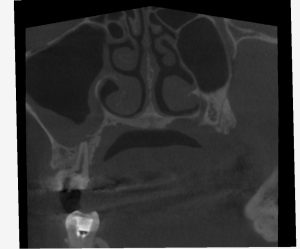

(術後6ヶ月のレントゲン、CT)

今回は全ての根管において、治癒が認められた。

治療前の症状も全て改善され、最終補綴へ移行した。